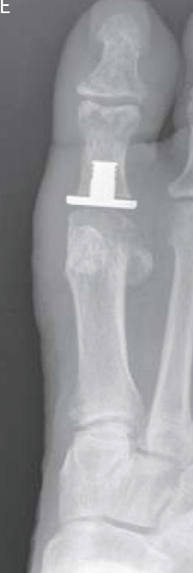

Artroplasti: MTP eklem yüzeyleri çıkarılarak yapay bir eklem yerleştirilmesidir. Bu ameliyat ağrıyı hafifletebilir ve eklem hareketini koruyabilir.

Artroplasti yapılmış hastanın röntgen filmi